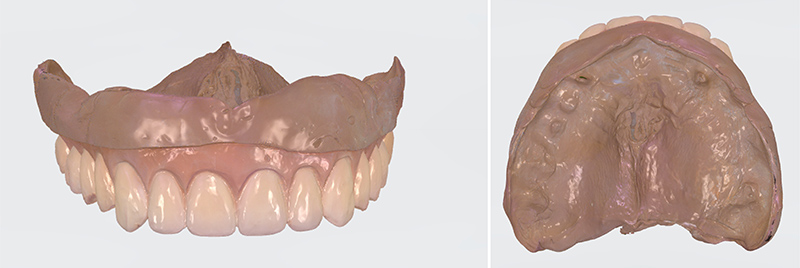

Fig. 02 : numérisation d’empreintes physico-chimiques ou de prothèses existantes.

Utilisée en mode intra-oral, elle permet de numériser les crêtes édentées de patients ne disposant pas de références prothétiques existantes et/ou exploitables.

Fig. 03 : numérisation des crêtes édentées d’un patient.

Il convient toutefois de rappeler que l’empreinte optique ne permet pas l’enregistrement de la dépressibilité muqueuse ni du joint périphérique. Elle autorise donc uniquement la réalisation d’empreintes primaires chez ces patients. L’empreinte obtenue est de nature muco-statique et s’accompagne fréquemment de surextensions, rendant nécessaire, dans un second temps, la réalisation d’une empreinte anatomo-fonctionnelle selon une technique conventionnelle à l’aide d’un porte-empreinte individuel(12).

Dans ce contexte, le flux de travail numérique actuellement privilégié pour la fabrication des prothèses amovibles complètes repose le plus souvent sur une approche hybride. Il débute par la réalisation d’une empreinte conventionnelle, obtenue à l’aide d’un porte-empreinte individuel imprimé, de la prothèse existante du patient ou d’un duplicata de cette dernière. Cette empreinte physico-chimique est ensuite numérisée, soit directement au cabinet dentaire à l’aide d’une caméra utilisée en mode extra-oral, soit au laboratoire de prothèse ou au sein d’un centre de production. Les rapports occlusaux doivent également être numérisés puis superposés à l’empreinte via un algorithme informatique.